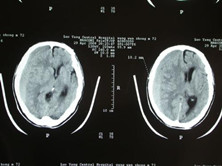

慢性硬脑膜外血肿

慢性硬脑膜外血肿罕见,是指受伤后2~3周以上的血肿。一般来说,受伤后13天以上,...

头部MRI、头部CT